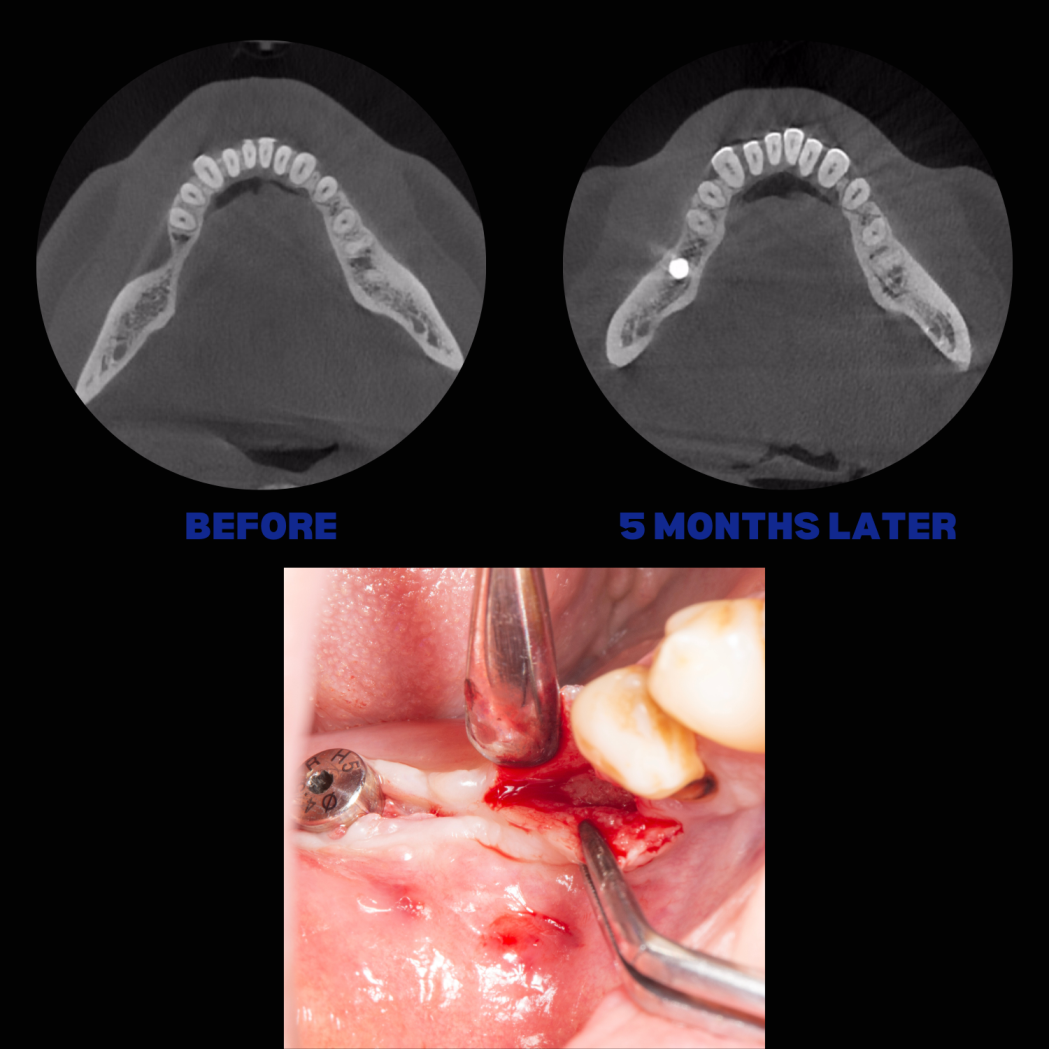

İmplant etrafındaki kemik açıklığını kemik grefti ile tedavi ettiğimiz vakamız.